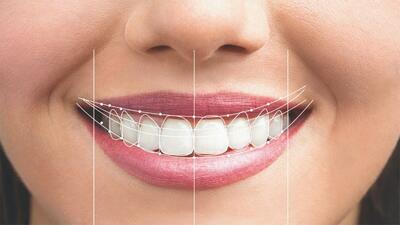

هر آنچه باید درباره آزمایشگاه ها و کلینیک های دندانپزشکی بدانید

رسیدگی به دهان و دندان یکی از کارهای مهمی است که سن و سال خاصی نمیشناسد. چکاپ دورهای و منظم دندانها به شما کمک میکند تا بتوانید همیشه دندانهای سالم و مرتبی داشته باشید و درد ناگهانی دندان به سراغ شما نیاید.

ارتودنسی دندان با شرایط پرداخت دو ساله و ضمانت نامه کتبی در تهران

اگر دچار ناهنجاری های فکی و دندانی هستید یکی از بهترین خدمات دندانپزشکی در این زمینه ارتودنسی است که میتواند تاثیر زیادی بر زیبایی و مرتب شدن دندان های شما داشته باشد.

پیدا و پنهان تبلیغات ایمپلنت ۳۰ ثانیهای !

یک متخصص جراحی دهان، فک و صورت، درباره تبلیغات ایمپلنت ۳۰ ثانیهای، توضیحاتی داد.